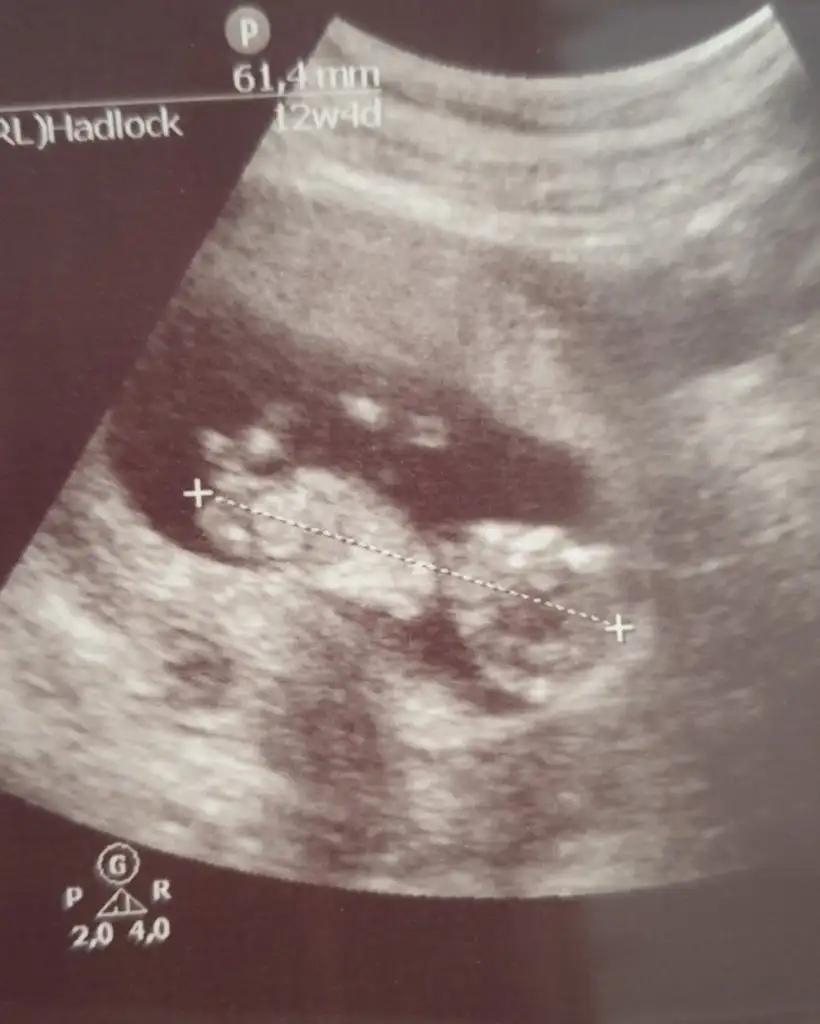

Benimkinide yorumlayın lütfen ilki 6+5 ikincisi 12+4

• 20210131_010440.webp

20210131_010440.webp

15 KB · Görüntüleme: 194

• 20210129_114145.webp

20210129_114145.webp

25 KB · Görüntüleme: 219